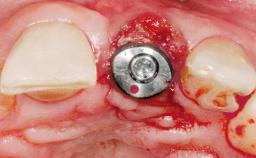

Late Placement of an Implant in a Maxillary Left Central Incisor Site

# of Implants 1

Type of Implants Two-Piece

Attachment Two-Piece

Bone Volume Deficient horizontally, requiring prior grafting